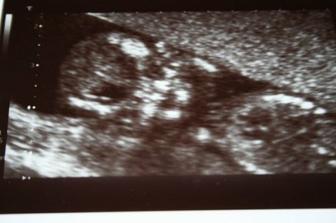

Mimi měří 40,8 mm a už je to malý človíček🙂 , odpovídá začátku 12tt.

27.7.2009 NT screening + biochemie negativní! (1,7 mm), mimi má CRL 69 mm, odpovídá 13+1.

25.8.2009 na ultrazvuku se miminko krásně hemžilo🙂...a zdá se, že je to holčička! Jsem z toho hodně překvapená, ale máme doma obrovskou radost.